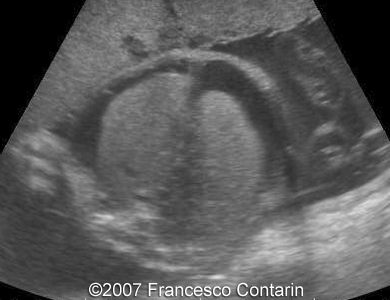

Images 9, 10. 29th week of pregnancy -  fetal ascites (left); and transverse plane through narrow thorax (right).

9

10